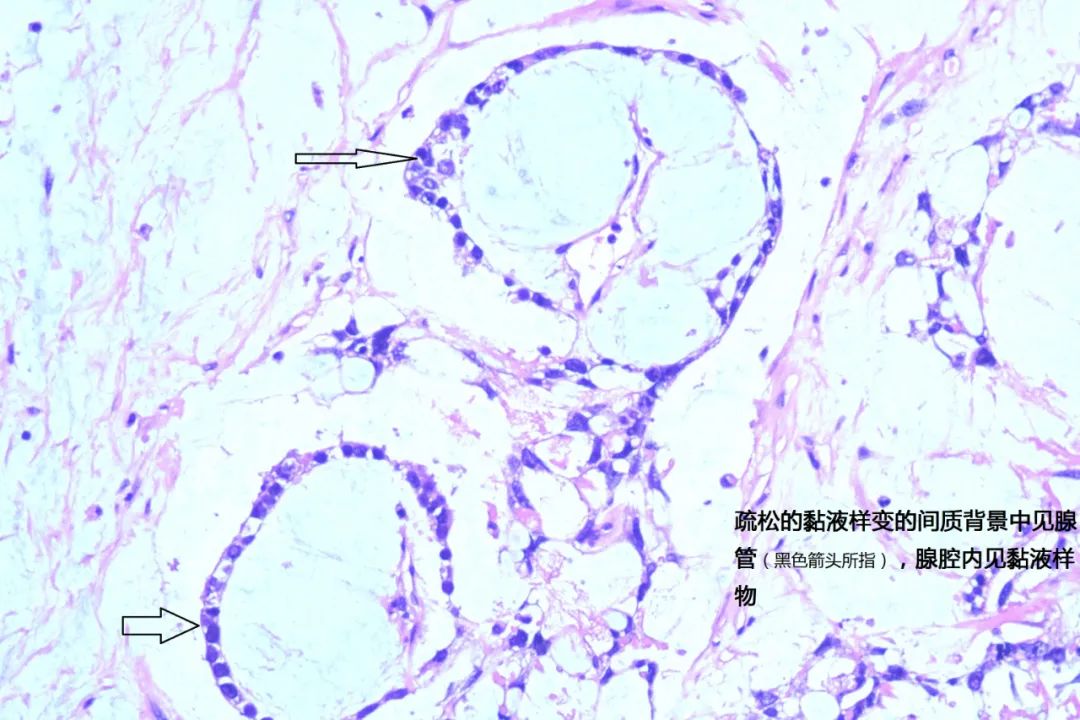

小颜在家人的陪同下来到我院妇科诊治,此时的小颜腹部已如孕6+月大小。住院后小颜莫名出现反复发热,抗感染治疗数日疗效欠佳。妇科主任米建锋经过系统全面的检查,考虑小颜的盆腹腔巨大肿物为卵巢恶性肿瘤的可能性极大,且发热考虑由该巨大肿瘤引起,建议尽快进行手术治疗。经与小颜家属沟通病情后决定行保留生育功能的手术治疗。术中发现巨大肿物来源于左侧卵巢,大小约25cm×20cm×12cm,包块与大网膜致密粘连,表面出血,腹腔内大量淡黄色积液约1500ml。在米建锋及普外科逄世江副主任医师的通力合作下,完整将小颜体内重二十余斤的肿物切除。米建锋表示,卵巢卵黄囊瘤又称内胚窦瘤,是一种原始生殖细胞肿瘤,恶性程度高,约占恶性卵巢生殖细胞肿瘤的20%,发病率仅次于无性细胞瘤,常见于儿童及育龄期女性,也有妊娠期发现。临床上由于肿瘤增长快,体积较大,又易有包膜破裂及腹腔内种植,往往起病急。腹痛是本病最常见的症状,肿瘤坏死、出血可使体温升高而有发热症状。首选的治疗方案为手术联合化疗,该肿瘤恶性程度高,但对化疗较敏感,手术恢复后可通过有效的联合化疗来延缓疾病的复发。